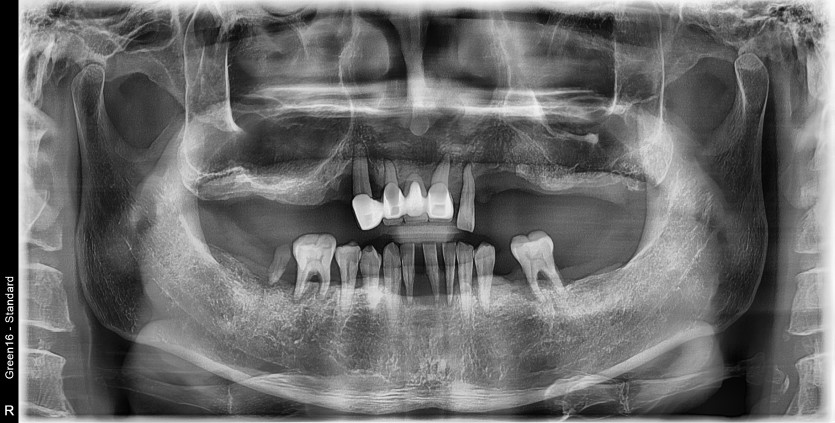

만 52세 전악 상악, 하악 전체 임플란트 증례

전악 전체 임플란트 증례입니다.

18개의 임플란트로 완성하였습니다.